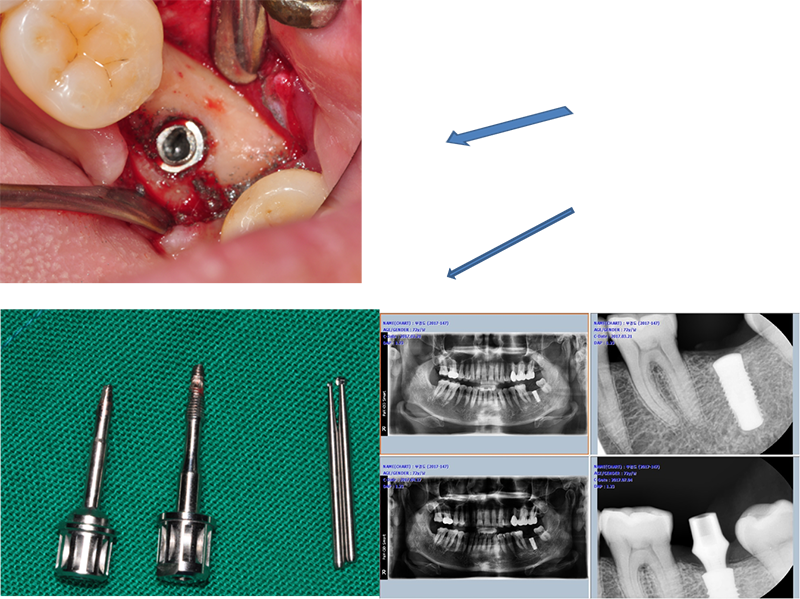

Submerged implant의 단점

Wide fixture(직경 5.5mm)

Sub type은 픽스쳐 직경과는 별 개로 어벗은 모두 동일한 사이즈다. 특징이자 장점이다. 픽스쳐가 부러지지 않아서 다행이다. 그러나 어벗의 밑동이 부러진 것도 매우 큰 합병증이다. 부러진 밑동을 깨끗하게 빼내는 것도 상당히 힘든 일이다.

37번 4.3 직경의 원플란트

결국 픽스쳐 제거

37번 abutment 파절, 뒤쪽에 8번이 보이고, fixture 직경이 5.0, 조금 흠집이 나도 된다는 생각으로 제거수술을

했다.

3번에

나눠서 겨우 제거한 경우